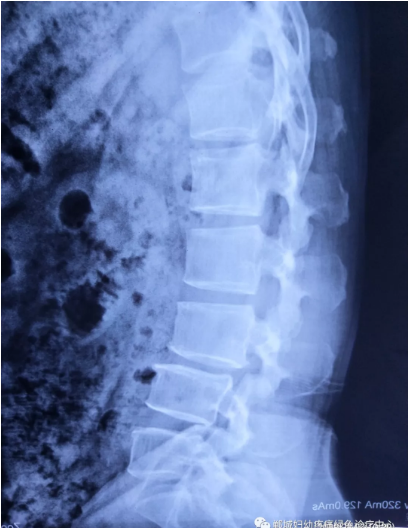

不經(jīng)意間聽到有人說醫(yī)院疼痛科可以不吃藥不打針,用無痛苦、無創(chuàng)傷的方法治療腰痛。陳女士就抱著試試看的心理來到了鄲城縣婦幼保健院疼痛科,疼痛科時慶祥主任詳細了解病情,結(jié)合腰椎磁共振及體征后告訴陳女士她不用手術(shù),通過腰椎脊柱定位周期減壓牽引系統(tǒng)(外星艙)也能解決腰痛、腰椎滑脫、腰椎反弓這些問題。陳女士未曾想到經(jīng)過十五天的治療后腰部及下肢放射性疼痛癥狀基本消失。陳女士感到十分激動與感謝,就在當?shù)匦l(wèi)生院做了一個腰椎正側(cè)位x片和之前的片子作對比,發(fā)現(xiàn)腰椎滑脫明顯改善。她說道:感謝鄲城縣婦幼保健院疼痛科的所有醫(yī)護人員、感謝外星艙脊柱減壓治好了我的腰痛,也感謝告訴我來這里的人,她的一句話,讓我省了好幾萬元的手術(shù)費!

治療后